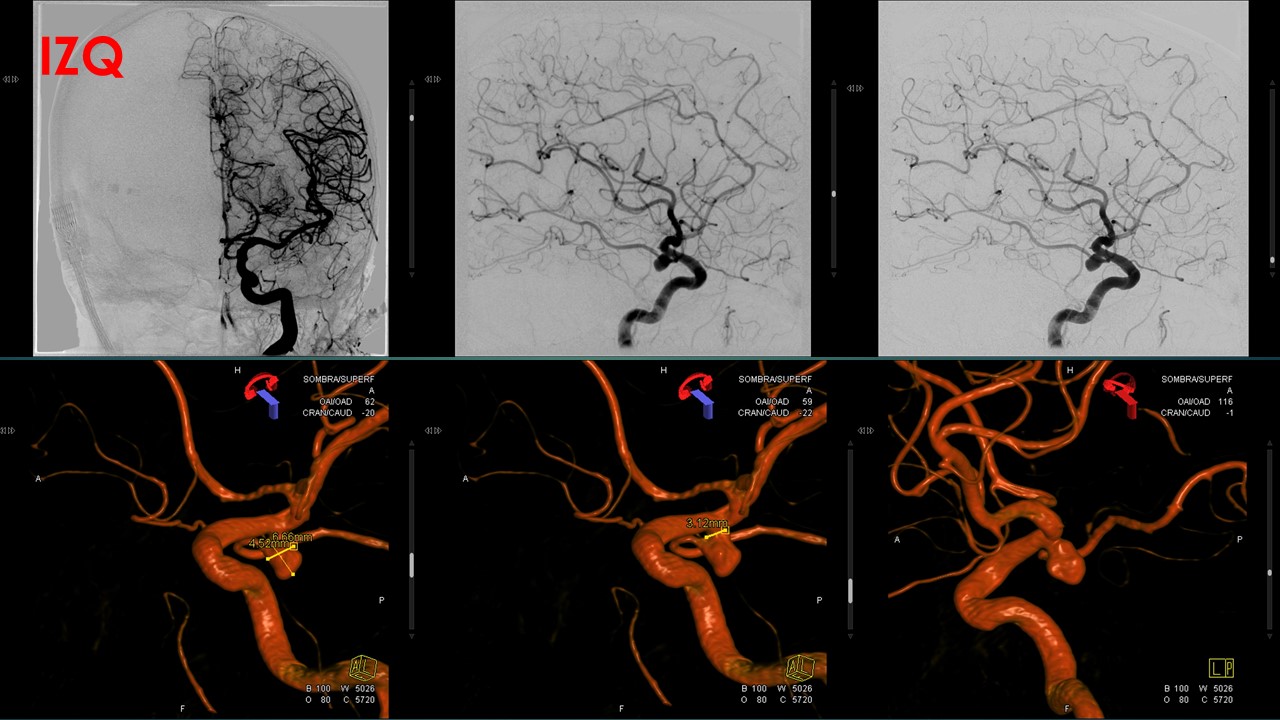

Procedimiento: Se realiza estudio diagnóstico confirmando la presencia de dos aneurismas localizado en

origen de comunicantes posteriores:

El derecho de 11x9x8mm con cuello de 5.3mm de morfología polilobulada, en su componente inferior se

origina la comunicante posterior.

El izquierdo de 6.6×4.5×6 con cuello de 3.12, comprometiendo el origen de comunicante posterior.

Se realiza microcateterismo selectivo del saco aneurismático derecho, con protección de balón Transform,

el cual se ubica en carótida previo a la bifurcación, posteriormente se dispone en su interior un total de 15

coils. En la serie angiográfica de comprobación se identifica persistencia de mínimo saco residual con

permeabilidad de la comunicante.

En un segundo tiempo se realiza microcateterismo selectivo del saco aneurismático izquierdo, con

protección de balón Transform, el cual se ubica en carótida previo a la bifurcación, posteriormente se

dispone en su interior un total de 9 coils. En la serie angiográfica de comprobación se identifica

persistencia de mínimo saco residual y ausencia de permeabilidad de comunicante posterior, pero con

adecuada permeabilidad de ACPI desde basilar.